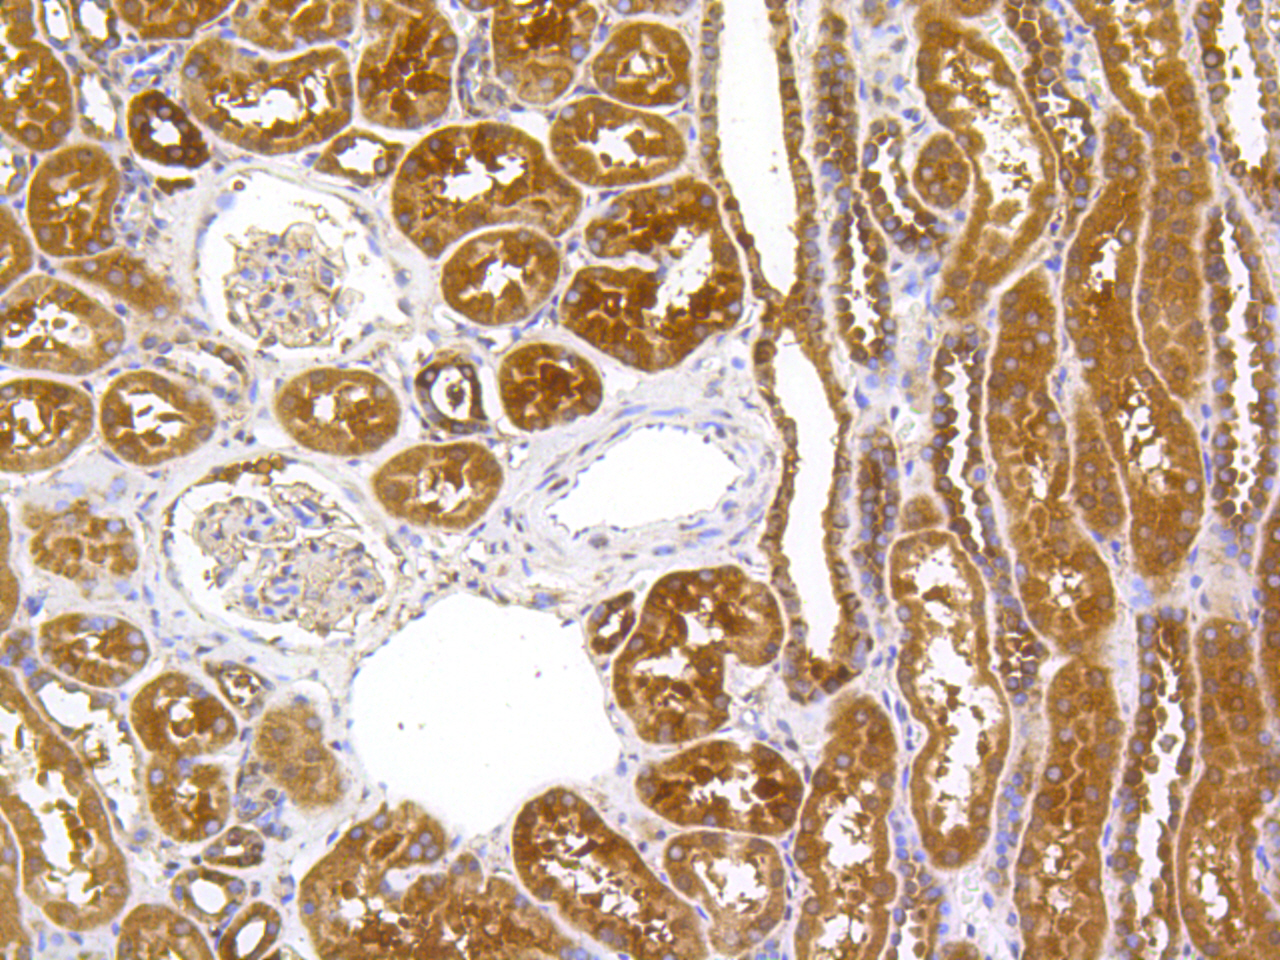

Immunohistochemical analysis of paraffin-embedded human kidney tissue using anti- HSC70 antibody. Counter stained with hematoxylin.